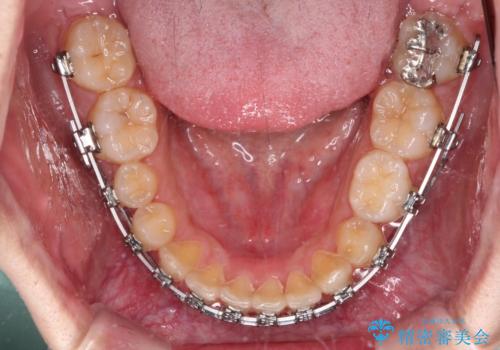

- 矯正装置

- メタルブラケット

ディープバイトの方は項合力が強大であることが特徴のため、仕上がりを重要視して、ワイヤー装置にて矯正治療を行うこととしました。